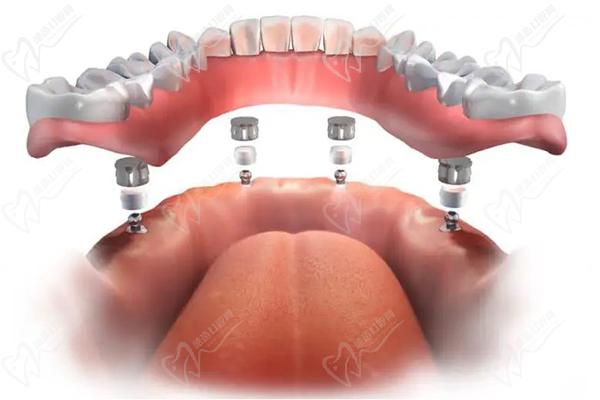

半口種植牙·集采種牙:21860元起

全口種植牙·集采:42720元起

廣州黃埔區(qū)種植牙半口牙多少錢(qián)?21860元起~6萬(wàn)元起

半口即刻負(fù)重種植牙:4萬(wàn)元起

廣州黃埔區(qū)全口種植牙價(jià)格表:42720元起~14萬(wàn)元起

全口種植牙·集采種牙:42720元起

全口即刻負(fù)重種植牙:8萬(wàn)元起